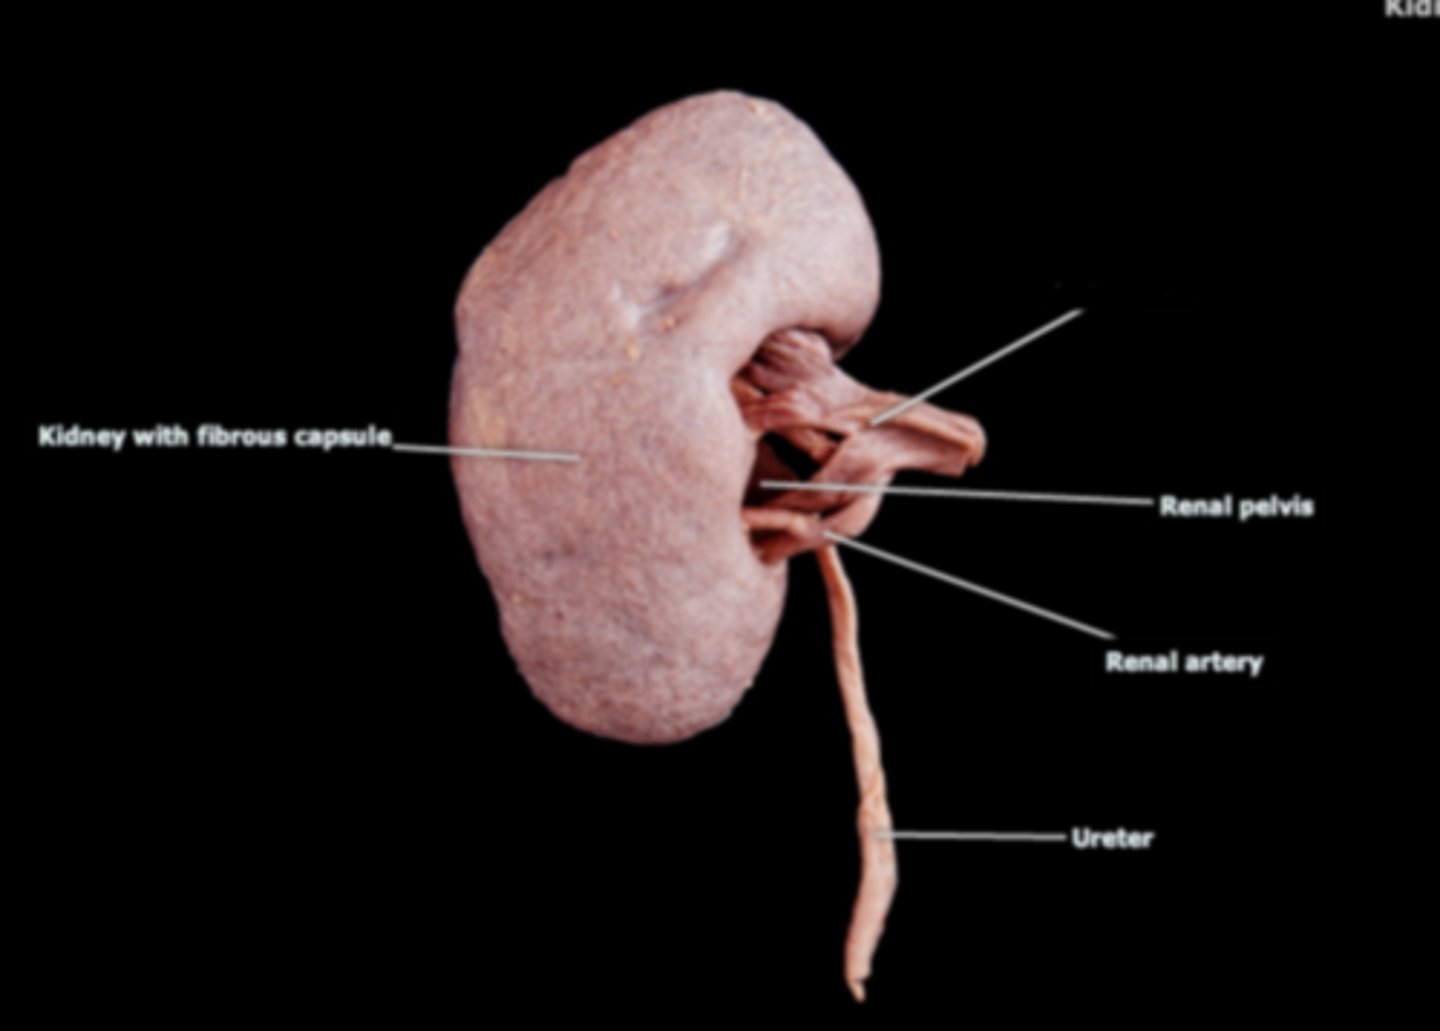

Right Kidney

Left Kidney

Renal Capsule

Renal Pelvis

Renal Hilum

Right Ureter

Left Ureter